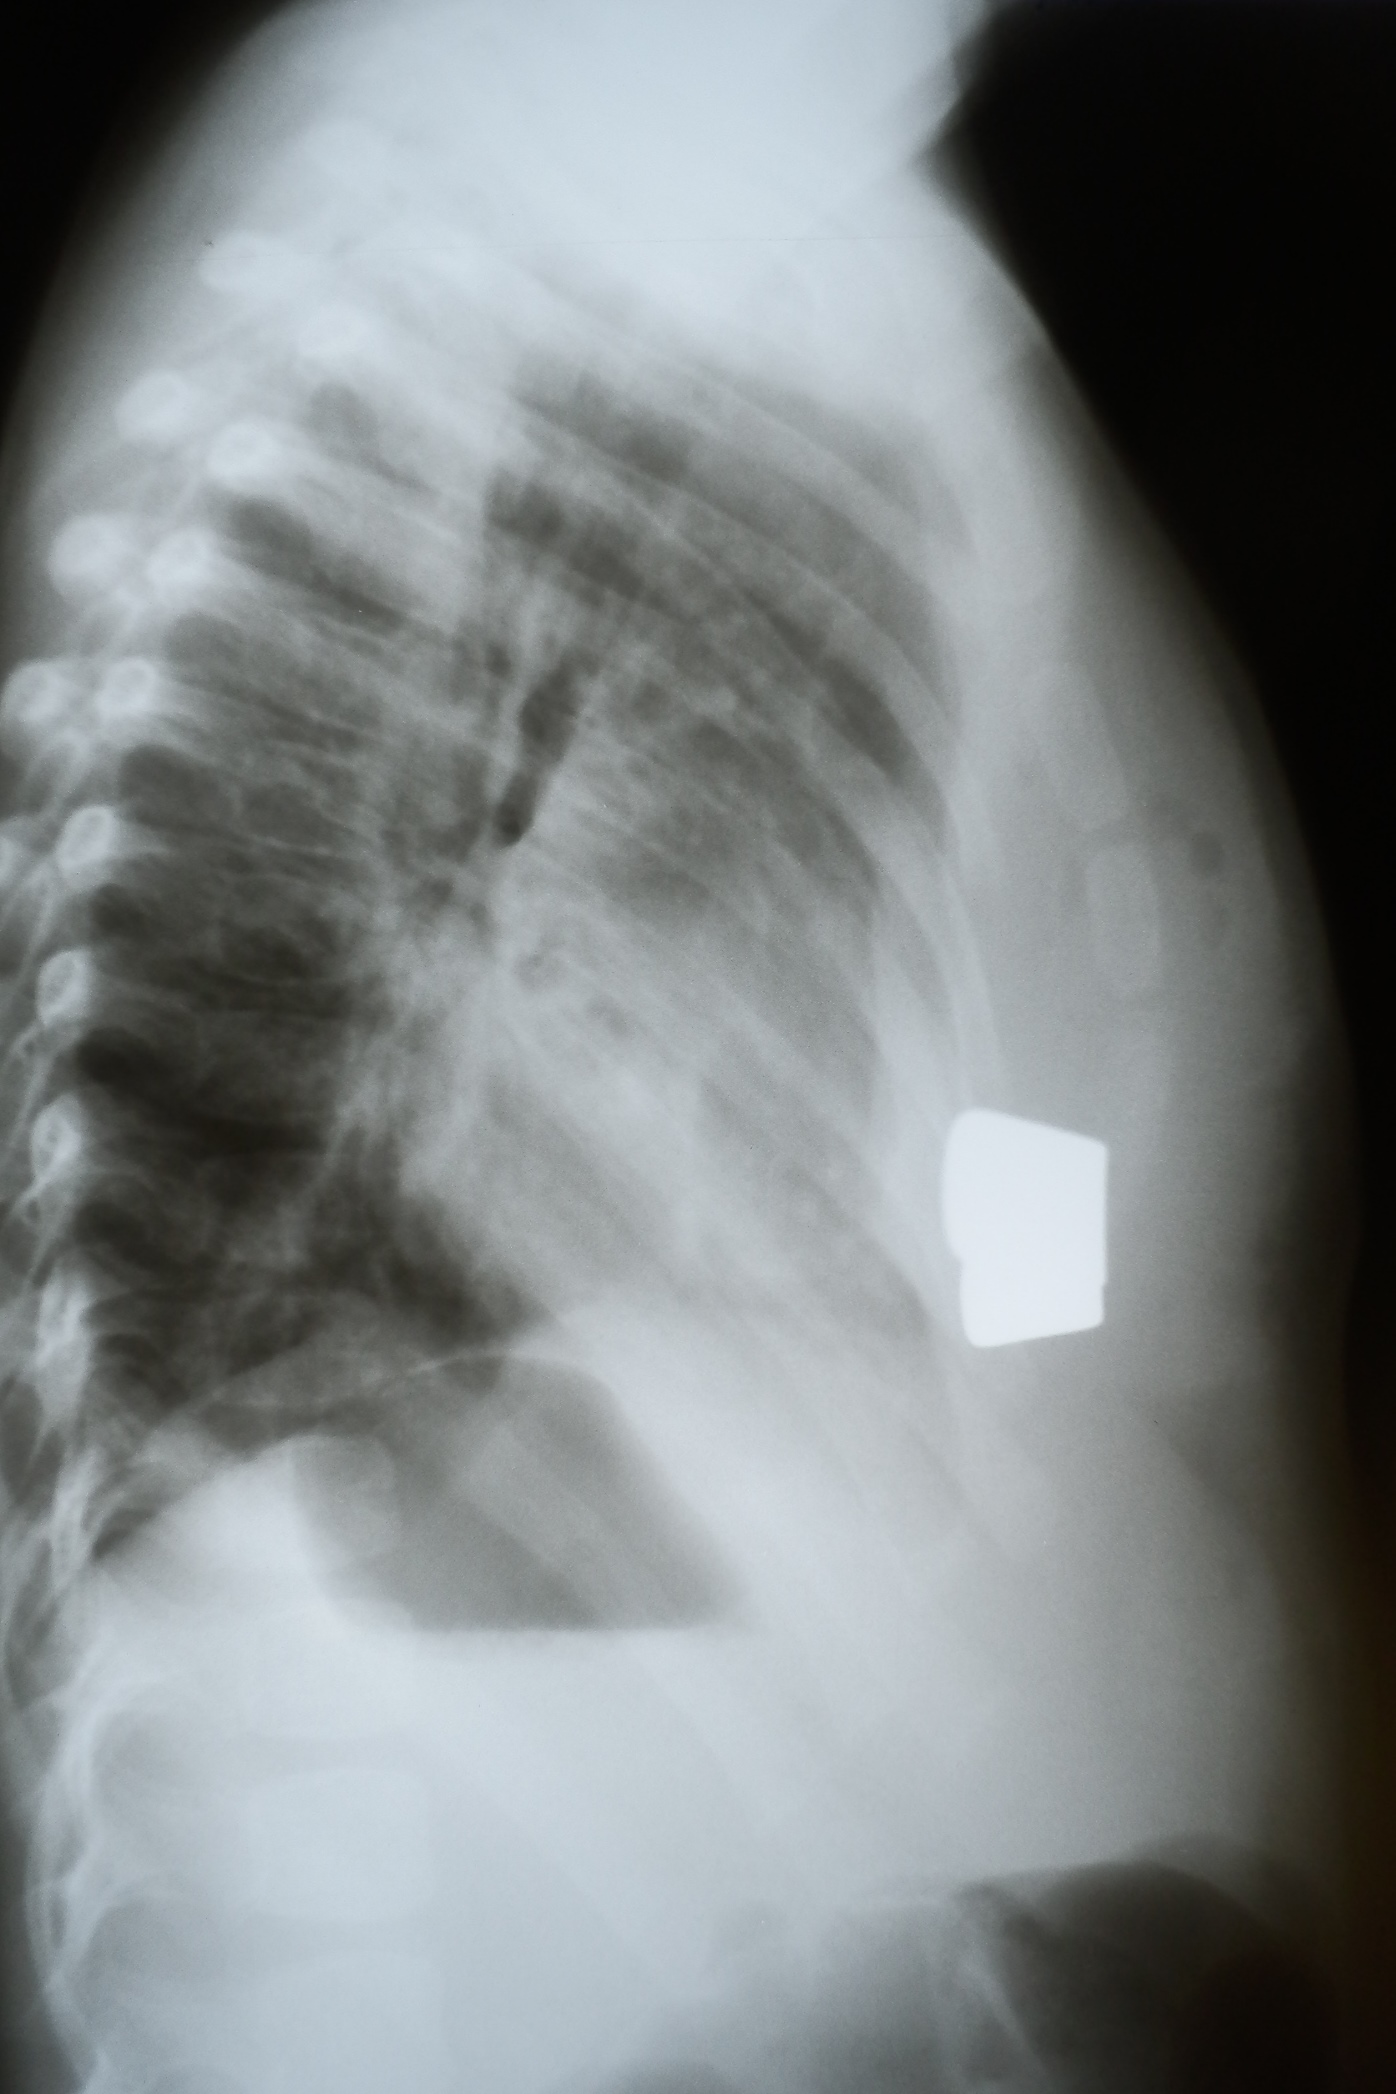

Рентгенограммы органов грудной клетки ребенка через 5 дней после операции

«Куриная грудь» выявляется хирургом в ходе физикального осмотра. Дополнительно назначается рентгенография, данные которой позволяют судить о характере и степени деформации. На рентгеновском снимке обычно видны следующие нарушения:

- увеличение загрудинного пространства;

- каплевидная форма сердца, его разворот по собственной оси и смещение;

отграничение друг от друга сегментов грудины в боковой проекции./li>